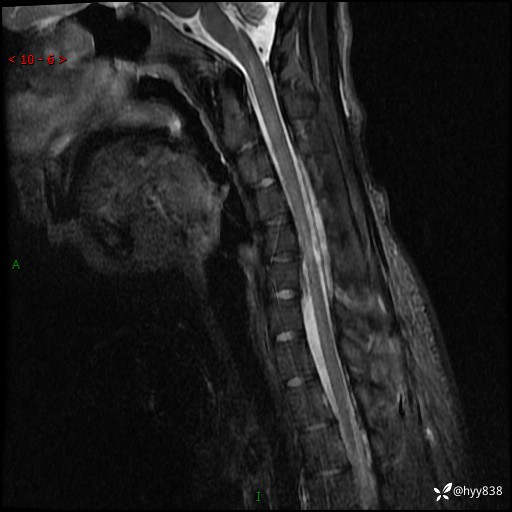

【患者信息】:男,17岁

【主诉】:右手抖动,乏力2年

【检查】:颈椎MRI

【临床诊断】:肌无力